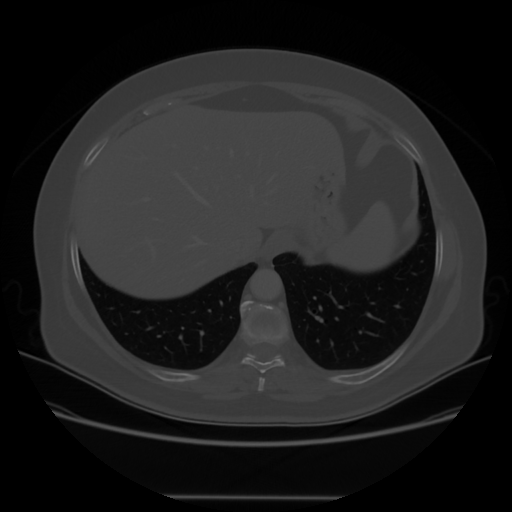

Generated VENOUS CT scan (A→B translation)

Lung window (WL -600, WW 1500 β†’ Low βˆ’1350, High +150)